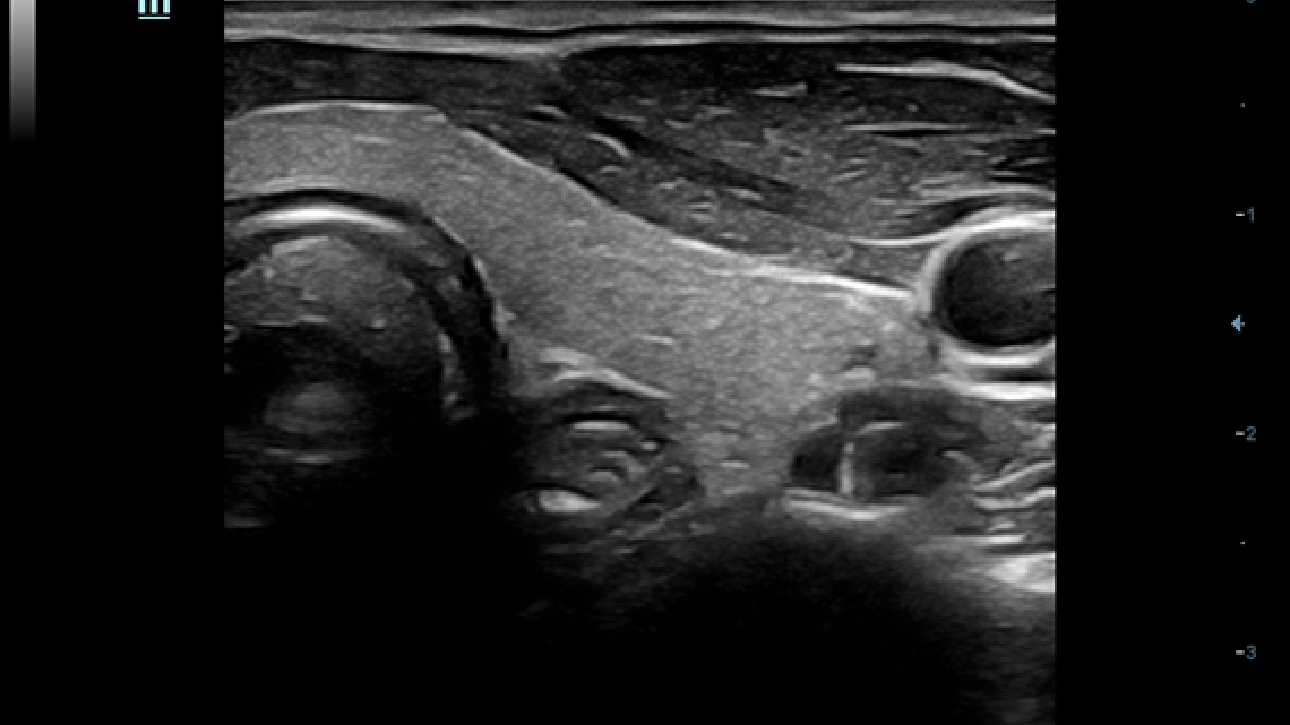

Klinische Bilder

Schallk?pfe